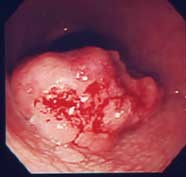

進行胃癌:

心窩部痛、食欲不振、黒色便を訴えて来院。抗潰瘍剤で症状は少し軽減しましたが、これまで胃の検査をしたことがなかったので、内視鏡検査を施行いたしました。胃に進行癌を認め、すぐに手術の方向で病院を紹介いたしました。癌は治癒切除(治ることが期待できる手術)でした。症状があって、検査を受けたことがない方は、積極的に検査を受けることをお勧めします。